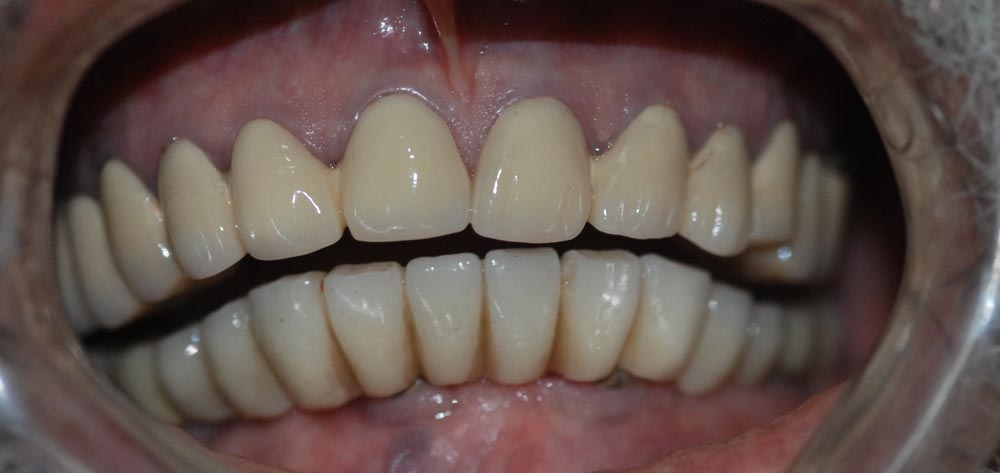

All on 4/ Teeth in a Day

Treatment Photos